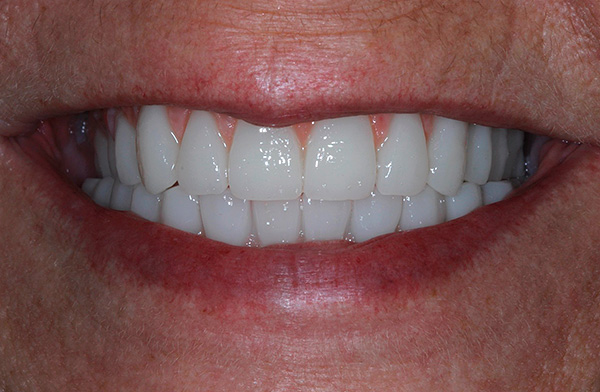

Os resultados das próteses usando a tecnologia All-on-4 parecem esteticamente agradáveis - exemplos são mostrados nas fotos a seguir.

Exemplo 2, foto antes do tratamento:

Depois:

A foto abaixo mostra um exemplo de aparência da dentadura ao usar as duas tecnologias - All-on-4 e All-on-6: